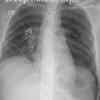

Deep sulcus sign.

Supine pneumothorax

Date: 04/28/2014

Views: 6292